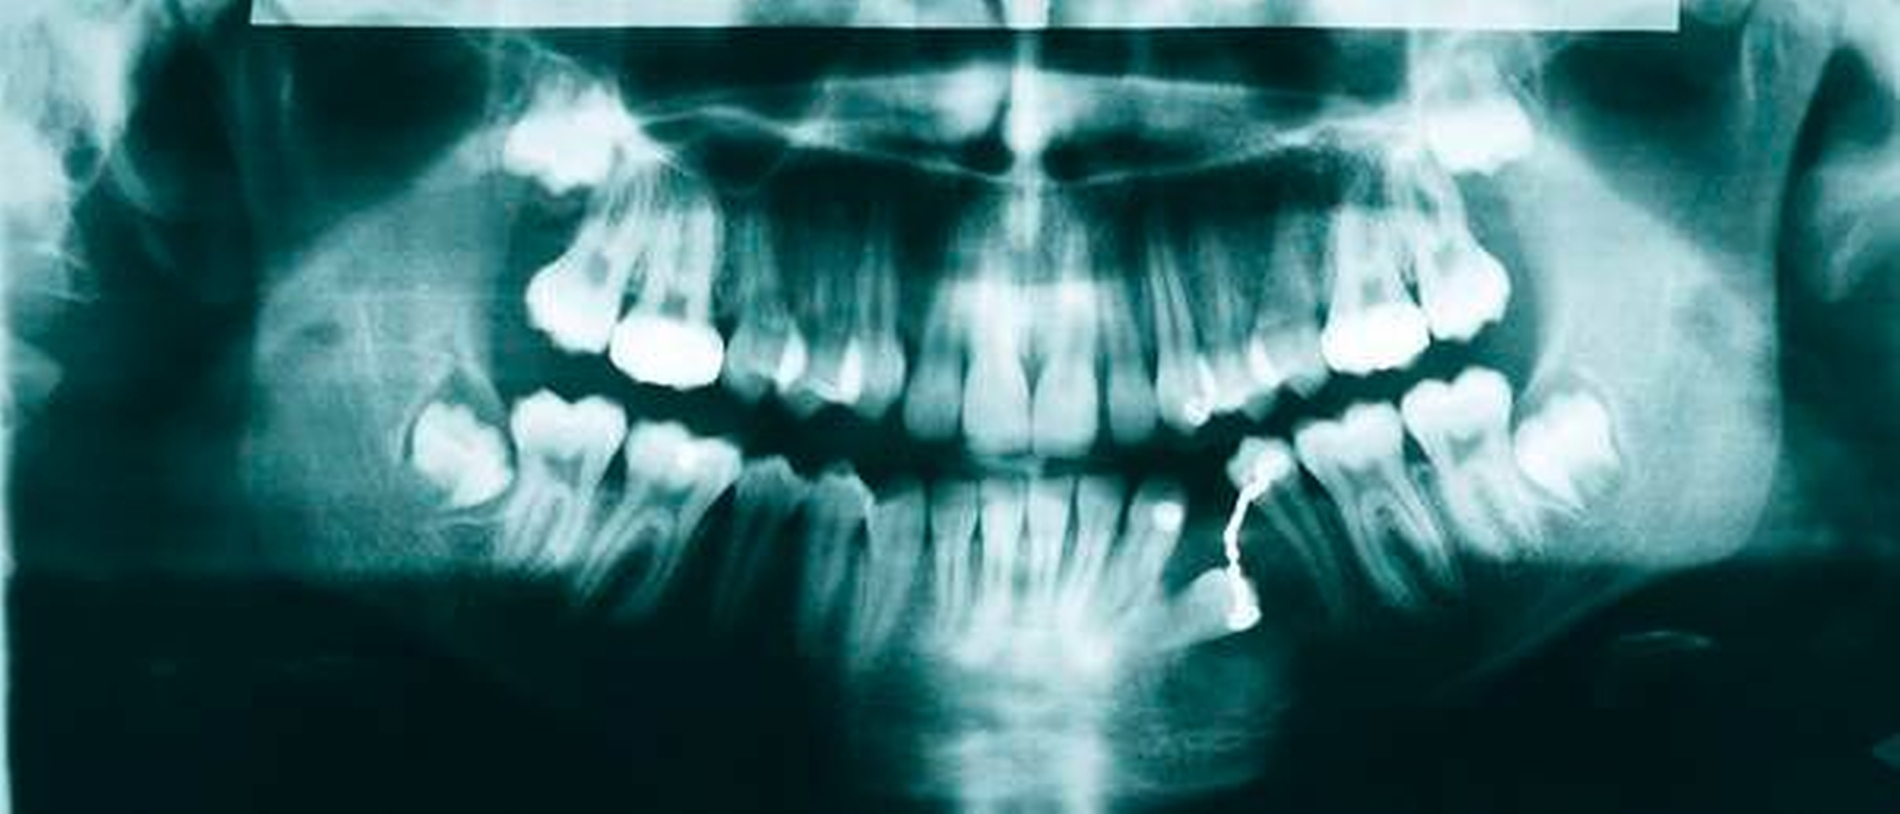

In den regelmäßigen klinischen Kontrollen zeigte sich eine stadiengerechte, reizfreie Wundheilung. Der Zahn 34 konnte mithilfe einer Multibandapparatur sukzessive aus der horizontalen Lage in die Lücke zwischen 33 bis 35 eingeordnet werden und „nahm“ dabei den ihn umgebenden Knochen mit.

In dem Zusammenhang fiel im radiologischen Verlauf vor allem die regrediente Zystenhöhle regio 33 bis 35 auf, die sich im Verlauf von zwei Jahren, sicherlich auch durch die Zahnbewegung durch das Zystenlumen, vollständig konsolidierte.

Die zwischenzeitliche Entfernung der Weisheitszähne diente der Okklusionsstabilisierung und der Prophylaxe eines Engstands (Abbildungen 6 bis 11). Technisch wurden ein Lingualbogen, ein Powerarm zur Elongation und im Verlauf der Behandlung eine feste Apparatur verwendet. An 34 wurde ein Bracket angebracht, ein Supercabble-Bogen als Huckepack-Bogen sowie ein SS-16x22-Trägerbogen eingesetzt.

Im abschließenden OPG war der Zahn 34 regelgerecht eingeordnet, die nach distal deviante Wurzelspitze ist aller Wahrscheinlichkeit nach der Verlagerung geschuldet (Abbildung 8).